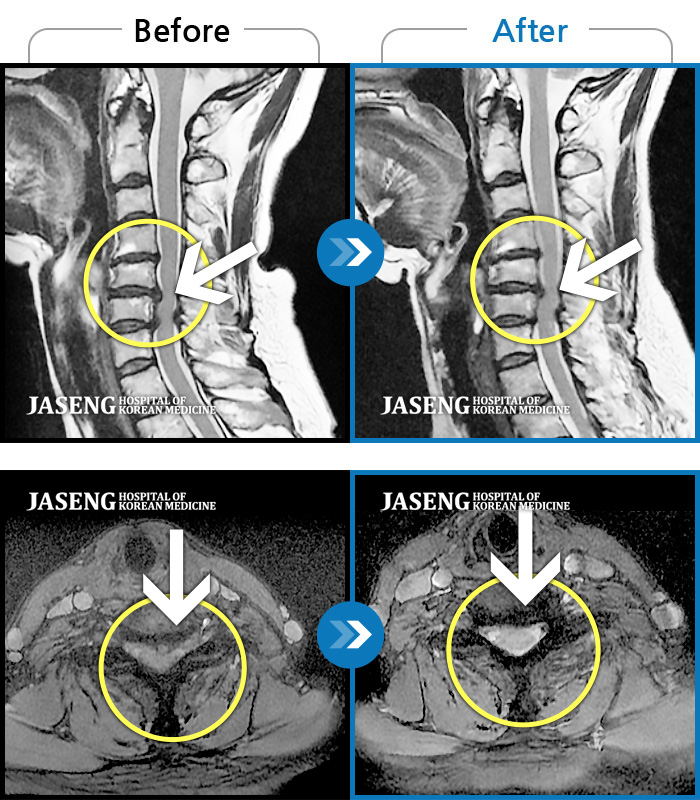

• 목디스크